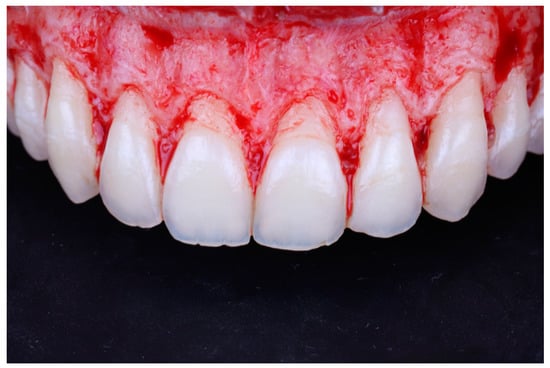

A full thickness mucoperiosteal flap was elevated past the mucogingival junction (Figure 7). The surgical guide was then placed again to determine the extent of osteoectomy needed (Figure 8), and the bone was marked with a round carbide bur. Using an end cutting carbide bur, osteoectomy was then performed; osteoplasty was performed after to remove buccal bone buttressing (Figure 9). The guide was then placed for a final check before internal vertical mattress sutures were placed using a monofilament non-resorbable material (5.0 Prolyne, Ethicon Inc, Somerville, NJ, USA) and hemostasis was ensured.

Figure 9.

Bone level after osteoectomy and osteoplasty.